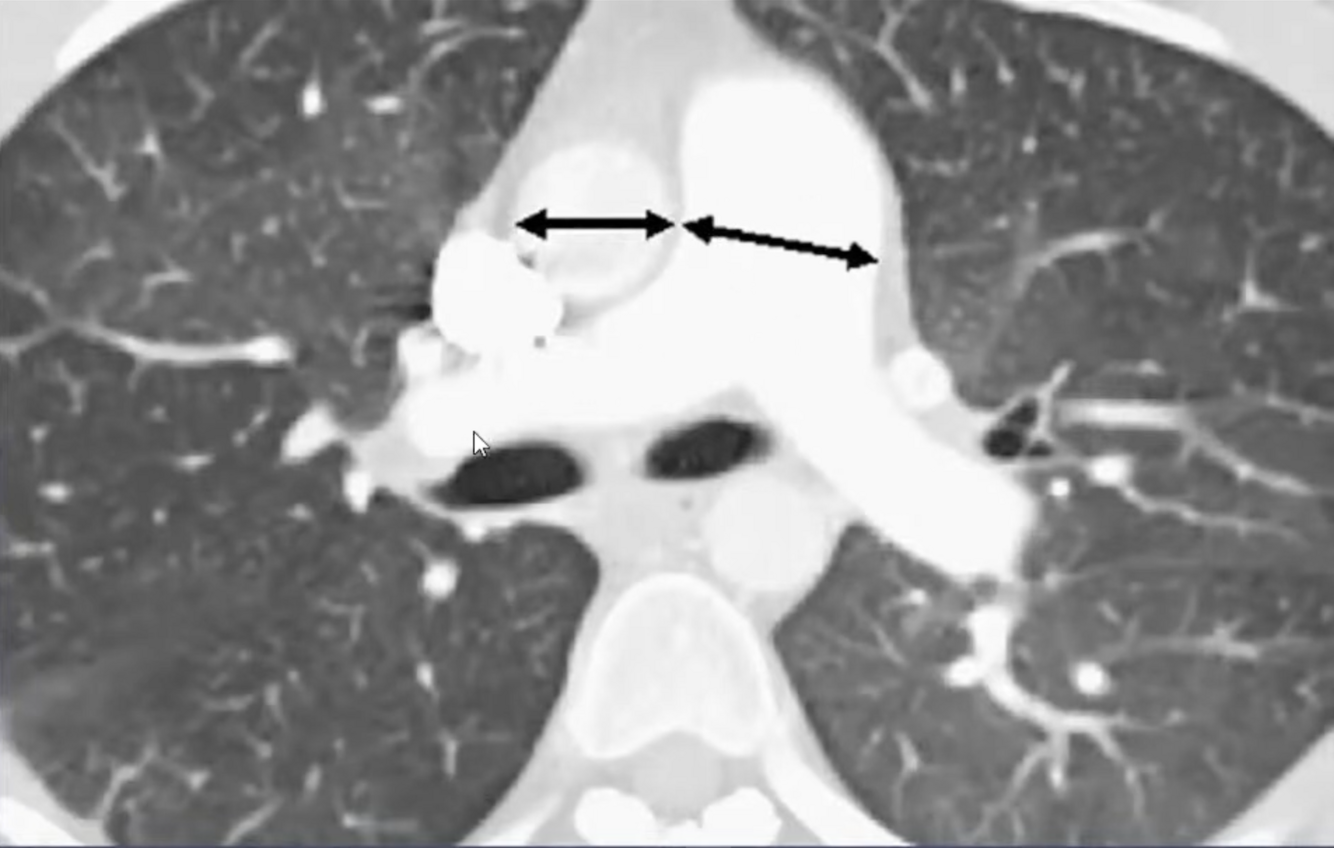

8

A

Hipertensão arterial pulmonar

9

Sinais radiológicos da HAP

• Dilatação de artéria pulmonar central

• Estreitamento abrupto ou afilamento de vasos pulmonares

• Aumento de VD e AD

• Dilatação de artérias brônquicas

• Atenuação em mosaico (perfusão pulmonar)